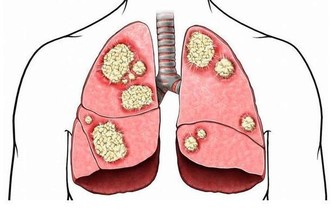

大腸癌也會導致慢性腹瀉,但可能不全是腹瀉,也可能表現為腹瀉和便秘反復交替發生。

3. 便便變細,排不盡

若是平時排的便便較粗,突然間變成了鉛筆一般的柔軟細便,並且總有排不盡的感覺,就要特別注意有可能是大腸癌導致的,需要高度警惕,必要時到正規醫院消化內科就診。